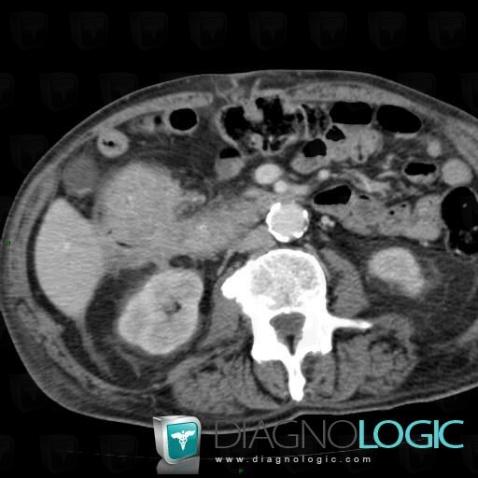

Colon cancer, Duodenum, CT

Here is the specific information in the key image above:

- Diagnosis Colon cancer, Location(s) Duodenum, with gamuts